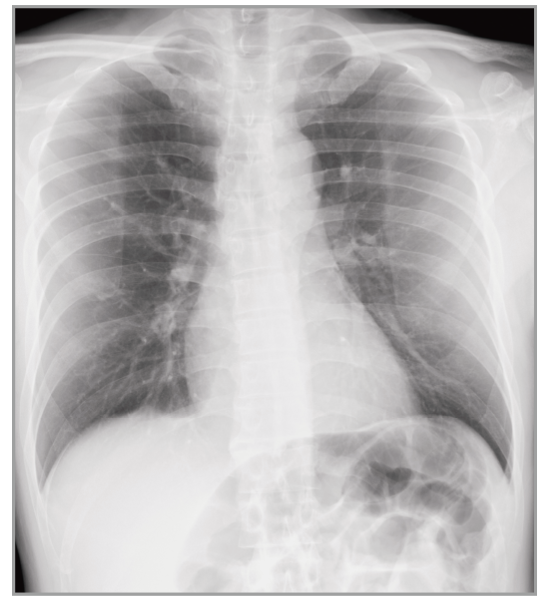

Virtual Grid

Provides a high quality image without using a grid

Virtual Grid processing corrects for the effects of scatter radiation. Without the need for a grid, Virtual Grid retains high contrast and image sharpness, while preventing the asymmetric density  resulting from misalignment of X-ray tube and detector. (Option)

Virtual Grid​

No Grid

Real Grid